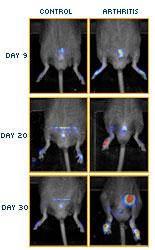

In the SCIENCE report, entitled "Identification of Splenic Reservoir Monocytes and Their Deployment to Inflammatory Sites," researchers at the Massachusetts General Hospital's Center for Systems Biology found that monocytes were held in concentration in the spleen and released to injured tissue sites in the body to participate in wound healing. As presented in the findings, the reporting scientists discovered and detailed the biologic pathway through the use of a series of advanced and integrated in vitro assays, microscopic readouts, and in vivo imaging methodologies, including magnetic resonance (MR) imaging combined with quantitative fluorescence molecular tomographic (FMT) imaging. Used together in a series of novel scientific models, the researchers developed correlated data sets to both identify this previously unidentified splenic reservoir of monocytes, and demonstrate the monocyte deployment to inflammatory sites in vivo. In the in vivo data analysis, non-invasive, quantitative FMT imaging using novel fluorescent molecular imaging agents, combined with MR imaging, clearly demonstrated not only the location, but also the biological activity of the recruited splenic monocytes at the disease site, thus helping to confirm "unambiguously the fate of monocytes from the spleen to the heart."